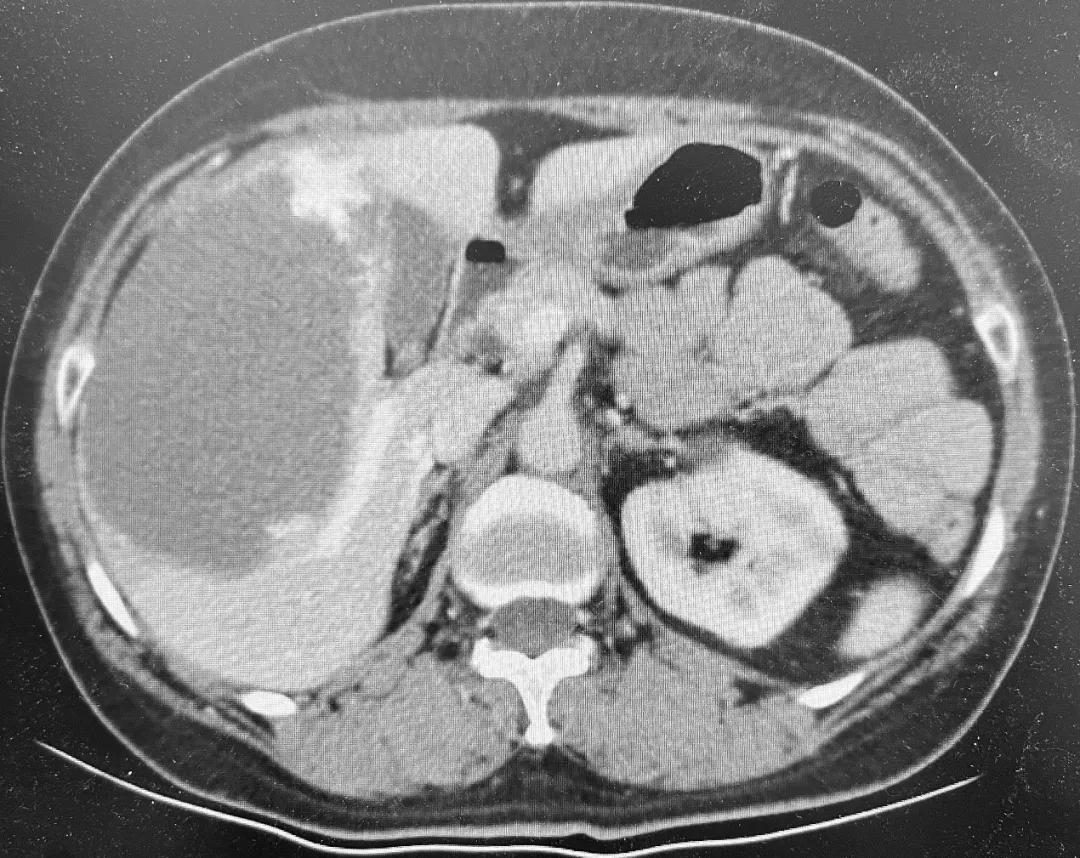

53岁的王女士平时一直身体很好,这次是来北京看儿子的。临近年关,孩子带着王女士做体检,超声检查偶然发现肝脏长了个13cm的肿物,进一步增强CT确诊为巨大肝血管瘤。

在心脏问题得到处理后,普外科重新将王女士收入院。术前评估发现王女士血管瘤与右肝的肝蒂和肝静脉关系密切,实施右半肝切除是相对容易的手术方式,但右半肝切除会损失20%左右的正常肝组织。在对影像进行详细研判的基础上,结合既往的肝脏手术经验,高鹏骥主任团队选择了难度相对更大但患者获益更多的血管瘤剥除手术。2022年1月6日,在麻醉团队和手术室护理团队的密切配合下,普外科成功为王女士实施了腹腔镜下巨大血管瘤剥除手术,术后在监护室短暂过渡后返回普通病房, 1周后王女士就完全康复出院了。